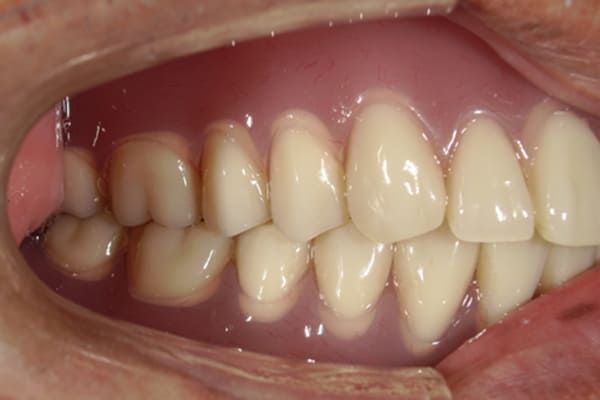

ご自身の歯に負担の少ないバネ、また見た目も改善

ご自身の歯に負担の少ないバネ

銀歯からセラミック歯に

バネをかける歯は繋げることで強度を増し、歯への負担を軽減し、歯の寿命を長くする設計へ。

バネがかかる歯の被せ物は、歯への負担を減らし、入れ歯が動きにくいようになる形態をあらかじめ付与することで、より入れ歯の機能が高まります。

治療を行う際、被せ物や入れ歯は、別々に考えるのではなく、一口腔単位としてお口全体のことを考え最良の治療計画を立てることが歯の寿命、機能効果を向上させるため、専門医としてこのことは常に心掛けて治療を行っています。